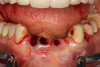

Fig 7. Radiograph showing the patient’s multiple implant restorations.

Figure 7

Figure 6 and Figure 7 depict a mature smile with many implant restorations. An analog impression was sent to the laboratory. The impression was scanned by the laboratory, a model was created virtually, and the implant dimensions and position were defined. The 3D surgical guide was fabricated (Figure 8), allowing the patient to receive his therapy swiftly and predictably. Tooth No. 8 was extracted, and the implant was placed and immediately loaded with an acrylic provisional treatment crown (Figure 9). The screw-retained treatment crown was fabricated in-office from a previously completed diagnostic wax-up.